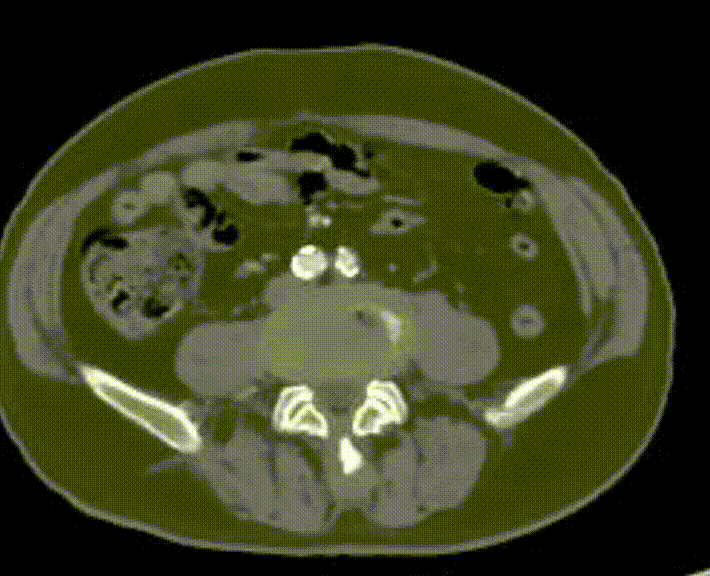

经导丝送入IVUS导管,股浅动脉近段重度狭窄、钙化明显,狭窄率大于90%

股浅动脉中远段及腘动脉重度狭窄、环周钙化明显

股浅动脉重度狭窄伴环周钙化